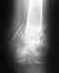

У мужа перелом пяточной кости.Вставили 4 спицы.В гипсе 10 дней.Когда засыпает сильно дергается нога,что это?Очень переживаем.